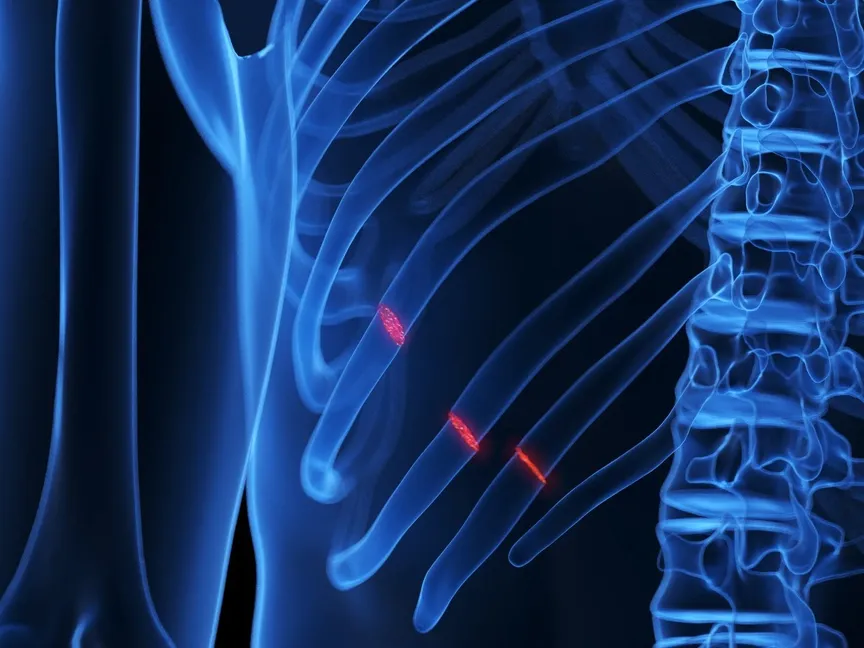

كسور الأضلاع هي إصابة شائعة تحدث عندما تتعرّض إحدى عظام القفص الصدري للكسر أو الشرخ. والأسباب الأكثر شيوعاً هي الصدمات العنيفة نتيجة لحوادث السقوط أو حوادث السيارات أو الرياضات التي تتضمن الاحتكاك البدني.

معظم كسور الأضلاع ما هي إلا شروخ. ورغم أن شروخ الأضلاع مؤلمة، لا تُسبب المشكلات التي يمكن أن تسببها الأضلاع المهشمة. فالحواف الحادة لكسور العظام يمكن أن تُلحق الضرر بالأوعية الدموية الرئيسية أو الرئتين وأعضاء الجسم الأخرى.

أسباب كسور الضلوع

الصدمات المباشرة، مثل الناتجة عن حوادث السيارات أو حالات السقوط أو إساءة معاملة الأطفال أو رياضات التلاحُم البدني، هي السبب الأكثر شيوعاً لكسور الأضلاع. يمكن أن تنكسر الأضلاع أيضاً بفعل الصدمات المتكررة الناتجة عن رياضات مثل الجولف والتجديف، أو الناتجة عن السعال الشديد لمدة طويلة.

مضاعفات كسور الضلوع

يمكن للضلع المكسور الإضرار بالأوعية الدموية وأعضاء الجسم الداخلية. وفي حال كسر أكثر من ضلع، يزداد احتمال التعرّض لهذه المخاطر.

وتختلف المضاعفات باختلاف الأضلاع المكسورة. تتضمن المضاعفات المحتملة:

- تمزق في الشريان الرئيسي للجسم المعروف باسم الشريان الأورطي. يمكن أن يخترق الطرف الحاد من كسر في أحد الأضلاع الثلاثة الأولى أعلى القفص الصدري أحد الأوعية الدموية الرئيسية، ومنها الشريان الأورطي.

- تمزق في الرئة. يمكن للطرف المدبب من ضلع أوسط مكسور أن يحدث ثقباً في الرئة ويسبب انخماصها.

- تمزق الطحال أو الكبد أو الكلى. نادراً ما ينكسر الضلعان السفليان بسبب قدرتهما على التحرك أكثر من الأضلاع العلوية والوسطى. لكن أطراف الضلع السفلي المكسور يمكن أن تسبب ضرراً خطيراً للطحال أو الكبد أو الكلى.